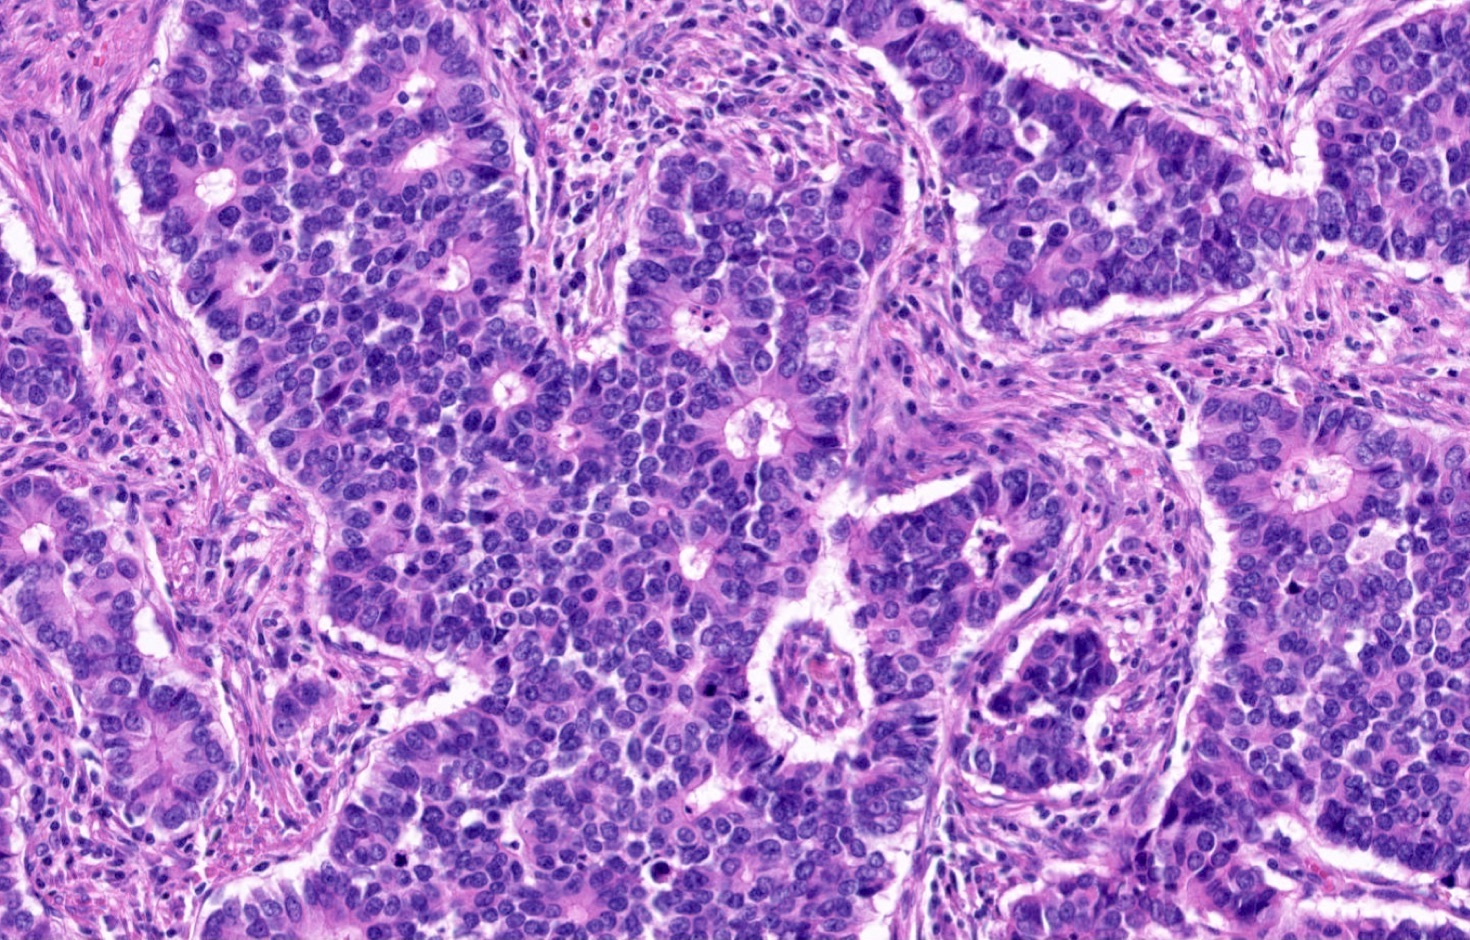

Microscopic (histologic) description

- Diagnostic criteria

- Neuroendocrine tumor with size ≥ 5 mm with < 2 mitoses/2 mm2 and absence of necrosis

- Neuroendocrine growth pattern (organoid, trabecular, rosette formation, nested) or pseudoglandular, follicular and papillary growth

- Tumor cells are uniform with a polygonal shape, round to oval nuclei with salt and pepper chromatin as well as inconspicuous nucleoli and moderate to abundant eosinophilic cytoplasm

- Spindle cells and clear cell features can be seen

- Stroma is fine and highly vascularized; hyalinization, cartilage or bone formation are possible

- Reference: Curr Oncol 2018;25:S86

Microscopic (histologic) images

Contributed by Philippe Joubert, M.D., Ph.D., Jijgee Munkhdelger, M.D., Ph.D. and Andrey Bychkov, M.D., Ph.D.

A 55 year old woman had a lower left lobectomy showing a well circumscribed flesh colored tumor. Histologic details are shown in the image above. Regarding this entity, which of the following statements is true?

A. CDX2 is usually negative in the lung and is useful to differentiate from a metastasis of an intestinal origin. The image shows a tumor with a trabecular pattern and pseudorosettes. The stroma is highly vascularized. Tumor cells are monotonous with scant to moderate eosinophilic cytoplasm. Nuclei are round to oval with salt and pepper chromatin and inconspicuous nucleoli. No mitoses are seen. These features are consistent with a typical carcinoid lung tumor.